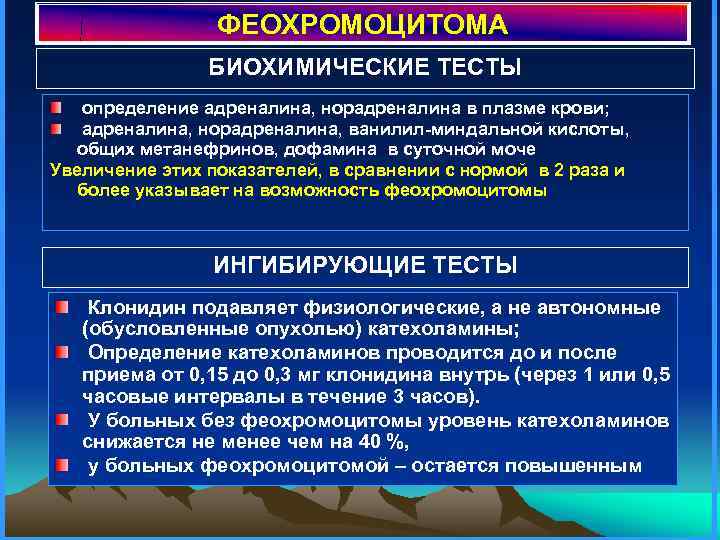

ФЕОХРОМОЦИТОМА БИОХИМИЧЕСКИЕ ТЕСТЫ определение адреналина, норадреналина в плазме крови; адреналина, норадреналина, ванилил-миндальной кислоты, общих метанефринов, дофамина в суточной моче Увеличение этих показателей, в сравнении с нормой в 2 раза и более указывает на возможность феохромоцитомы ИНГИБИРУЮЩИЕ ТЕСТЫ Клонидин подавляет физиологические, а не автономные (обусловленные опухолью) катехоламины; Определение катехоламинов проводится до и после приема от 0, 15 до 0, 3 мг клонидина внутрь (через 1 или 0, 5 часовые интервалы в течение 3 часов). У больных без феохромоцитомы уровень катехоламинов снижается не менее чем на 40 %, у больных феохромоцитомой – остается повышенным

ФЕОХРОМОЦИТОМА БИОХИМИЧЕСКИЕ ТЕСТЫ определение адреналина, норадреналина в плазме крови; адреналина, норадреналина, ванилил-миндальной кислоты, общих метанефринов, дофамина в суточной моче Увеличение этих показателей, в сравнении с нормой в 2 раза и более указывает на возможность феохромоцитомы ИНГИБИРУЮЩИЕ ТЕСТЫ Клонидин подавляет физиологические, а не автономные (обусловленные опухолью) катехоламины; Определение катехоламинов проводится до и после приема от 0, 15 до 0, 3 мг клонидина внутрь (через 1 или 0, 5 часовые интервалы в течение 3 часов). У больных без феохромоцитомы уровень катехоламинов снижается не менее чем на 40 %, у больных феохромоцитомой – остается повышенным